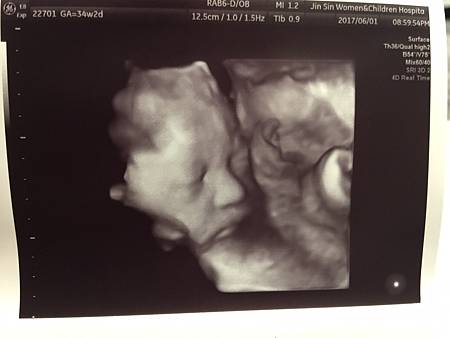

詠馨跟璟馨醫院的設備不太一樣,璟馨設備比較新一代,所以光是寶寶超音波照片,清晰度就真的有差。

N.T.九週和三十四週左右的超音波照,這不是高層次超音波檢查拍的唷,是不是超級清晰!!!

想當初一看到這樣的超音波照片,完全融化我的心,常常看到都會鼻子酸酸(感動說不出口,哈哈)